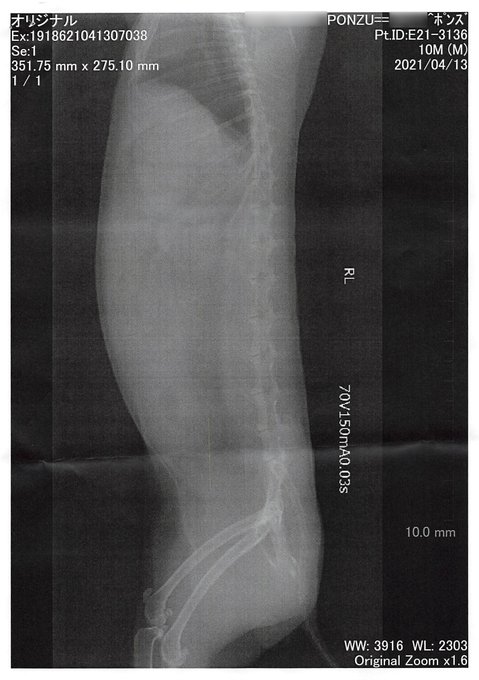

家の兎様、昼過ぎぐらいから何も食べてないらしい・・・・・動きも鈍いというかジッとして動かない・・・・嫁さんが病院に連れてった・・・・ pic.twitter.com/m5MIhVjAOn

軽い毛球症的な奴だったらしい、注射と薬飲んで帰ってきたら凄い元気になった・・・・・

私の仕事中になんか家の兎さんの調子が悪い、という事でいろいろあたふたして結果としては

★【三鷹の24時間営業動物病院にGO】わが家の兎さん、急に食べなくなり動かなくなって病院へ【毛球症的な奴か?】

こういう事に。餌食べないし、目に見えて動きが鈍いし本当心配した・・・・

帰ってきた兎さんは非常に元気で餌は食べ始まるし動きまくるし、ひとまずよかった・・・・・

ブログ書きました。【三鷹の24時間営業動物病院にGO】わが家の兎さん、急に食べなくなり動かなくなって病院へ【毛球症的な奴か?】: YUU MEDIA TOWN@Blog www.yuumediatown.com/diary/mt001/ar… pic.twitter.com/duUeRZfBYQ